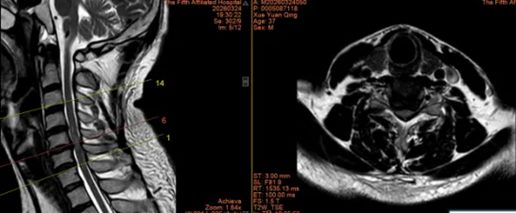

1.东莞市薛先生36岁

术前:依托高分辨率CT、MRI及神经电生理监测,进行三维可视化手术规划

术中:在超声骨刀辅助下开展颈前路、颈后路或后路+前路等术式,并在神经电生理监护下确保减压彻底、置钉安全。